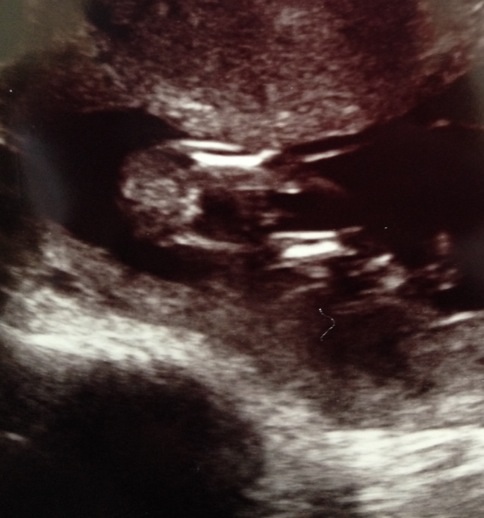

Here is a nub tooAttachment 18526

Definitely girl with that nub at 14 wks!

Yah really! Nub is all girl!

Yep, all girl! Congrats! x